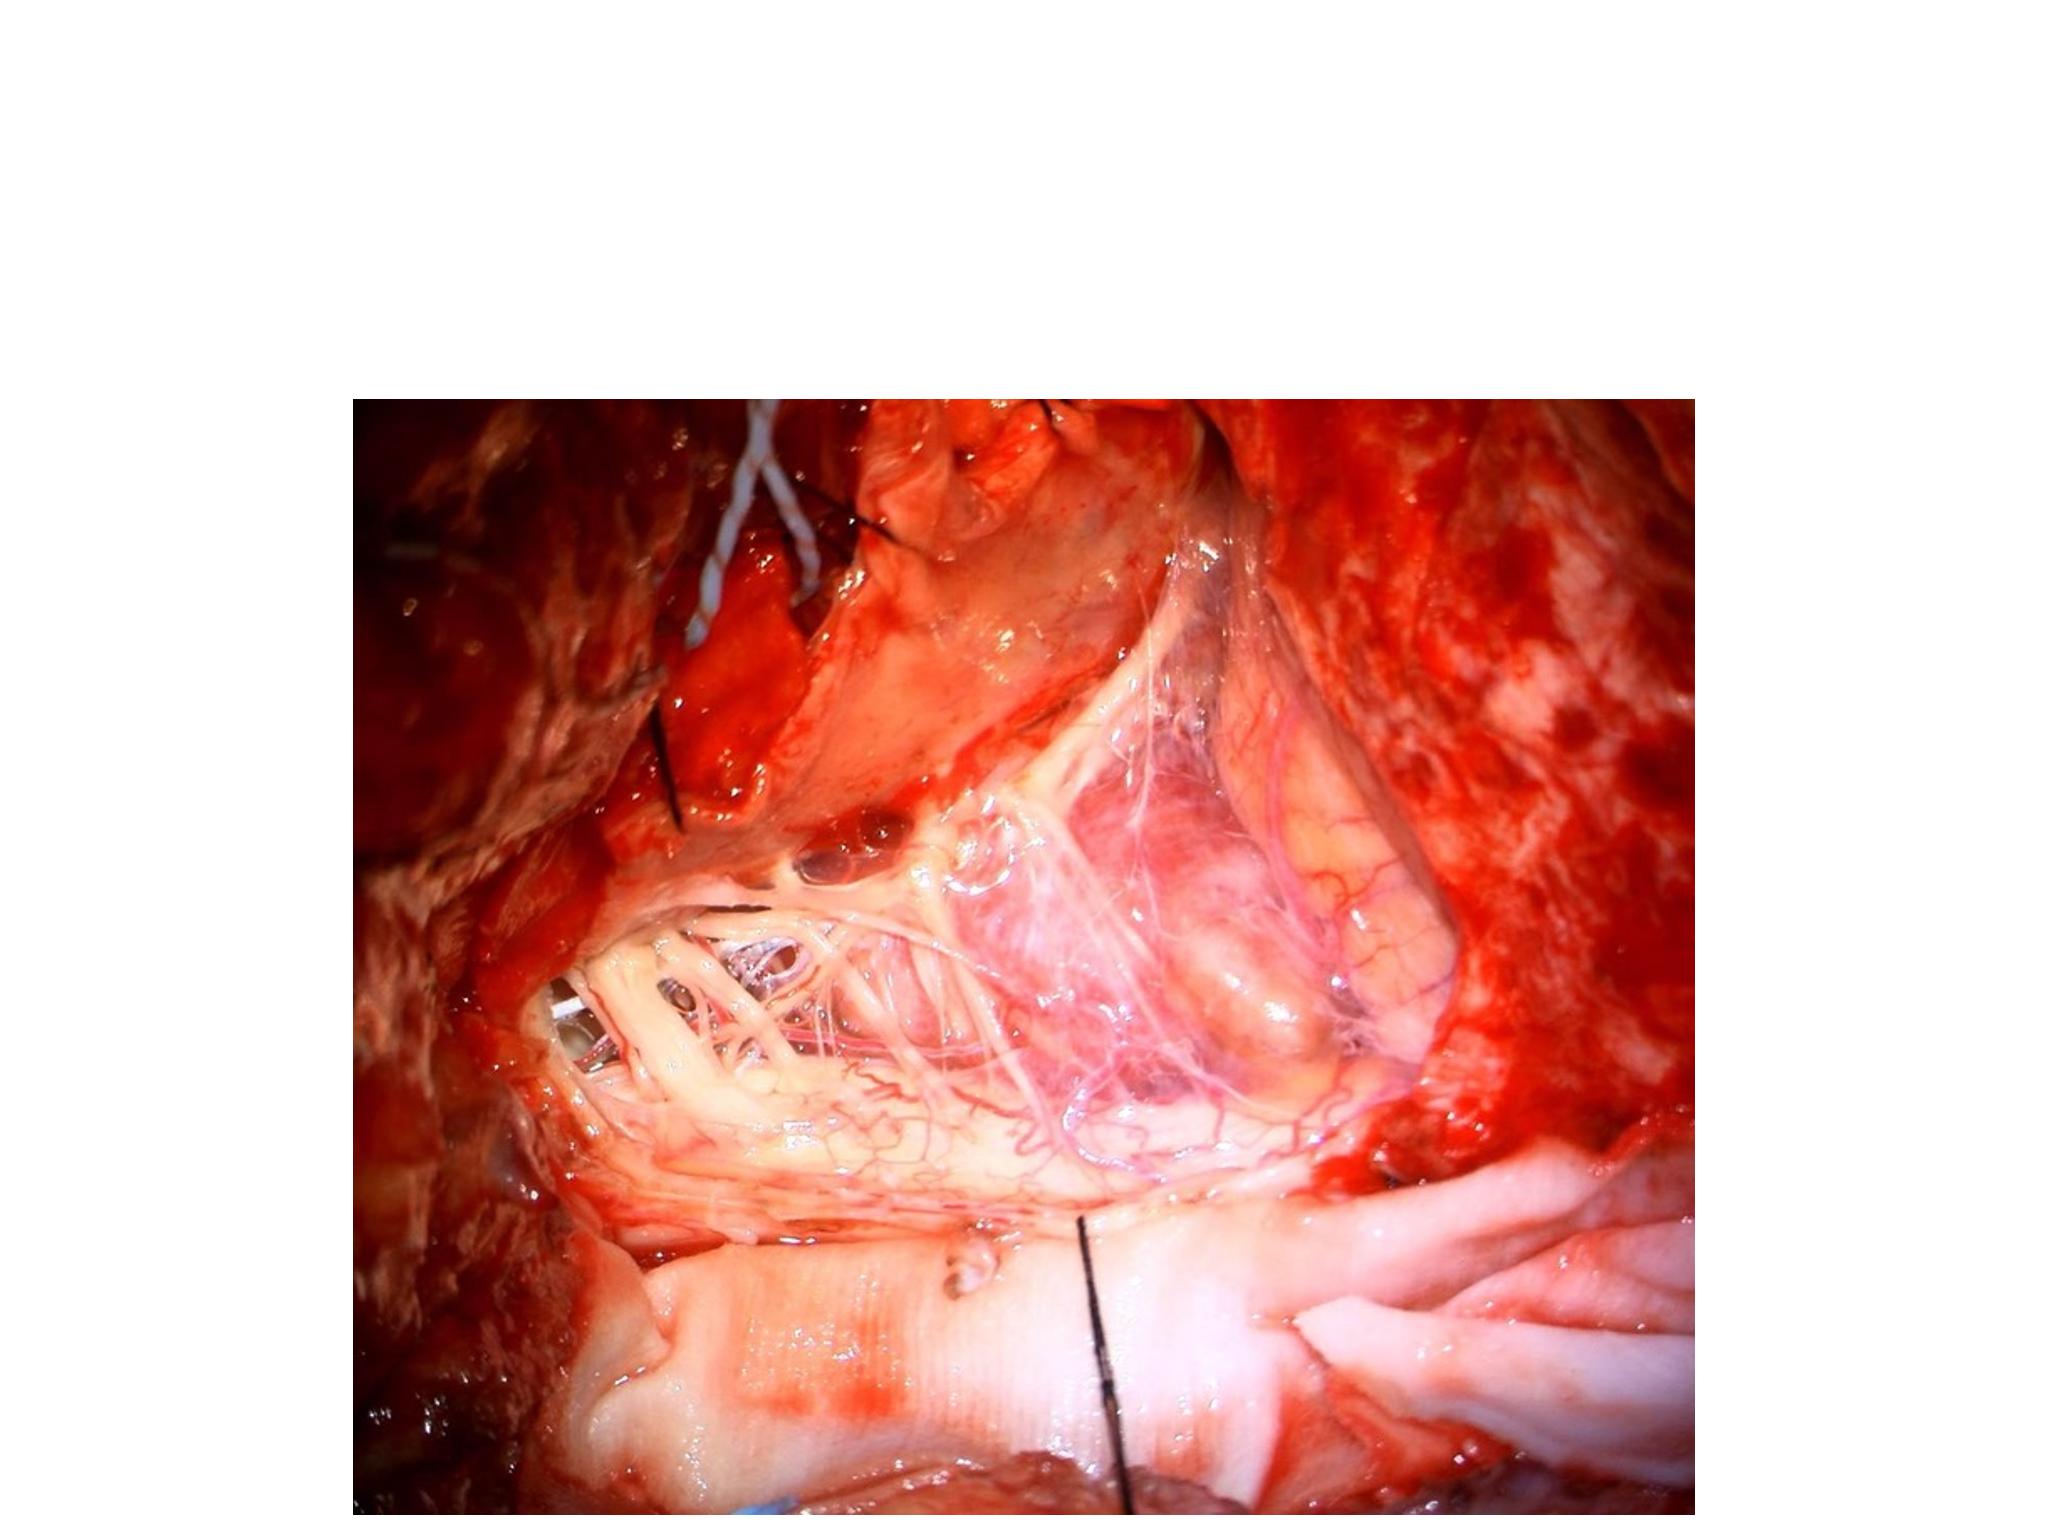

汇报一例后颅底肿瘤手术。为枕骨大孔巨大腹侧型脑膜瘤,该患者高龄,同时合并肺Ca,术前2周急性加重,枕骨大孔疝前期表现,术前已有延髓压迫及后组颅神经麻痹表现。经详细评估后采用远外侧经髁窝入路,最大化显露,重点保护延髓、后组颅神经,尽可能“零骚扰”。术中肿瘤质地韧,血供一般,与肿瘤上极与后组颅神经黏连紧密,最终99%切除,残留约1%,术后顺利康复出院,无新发症状,为后续进行肺部病变化疗创造有利条件。